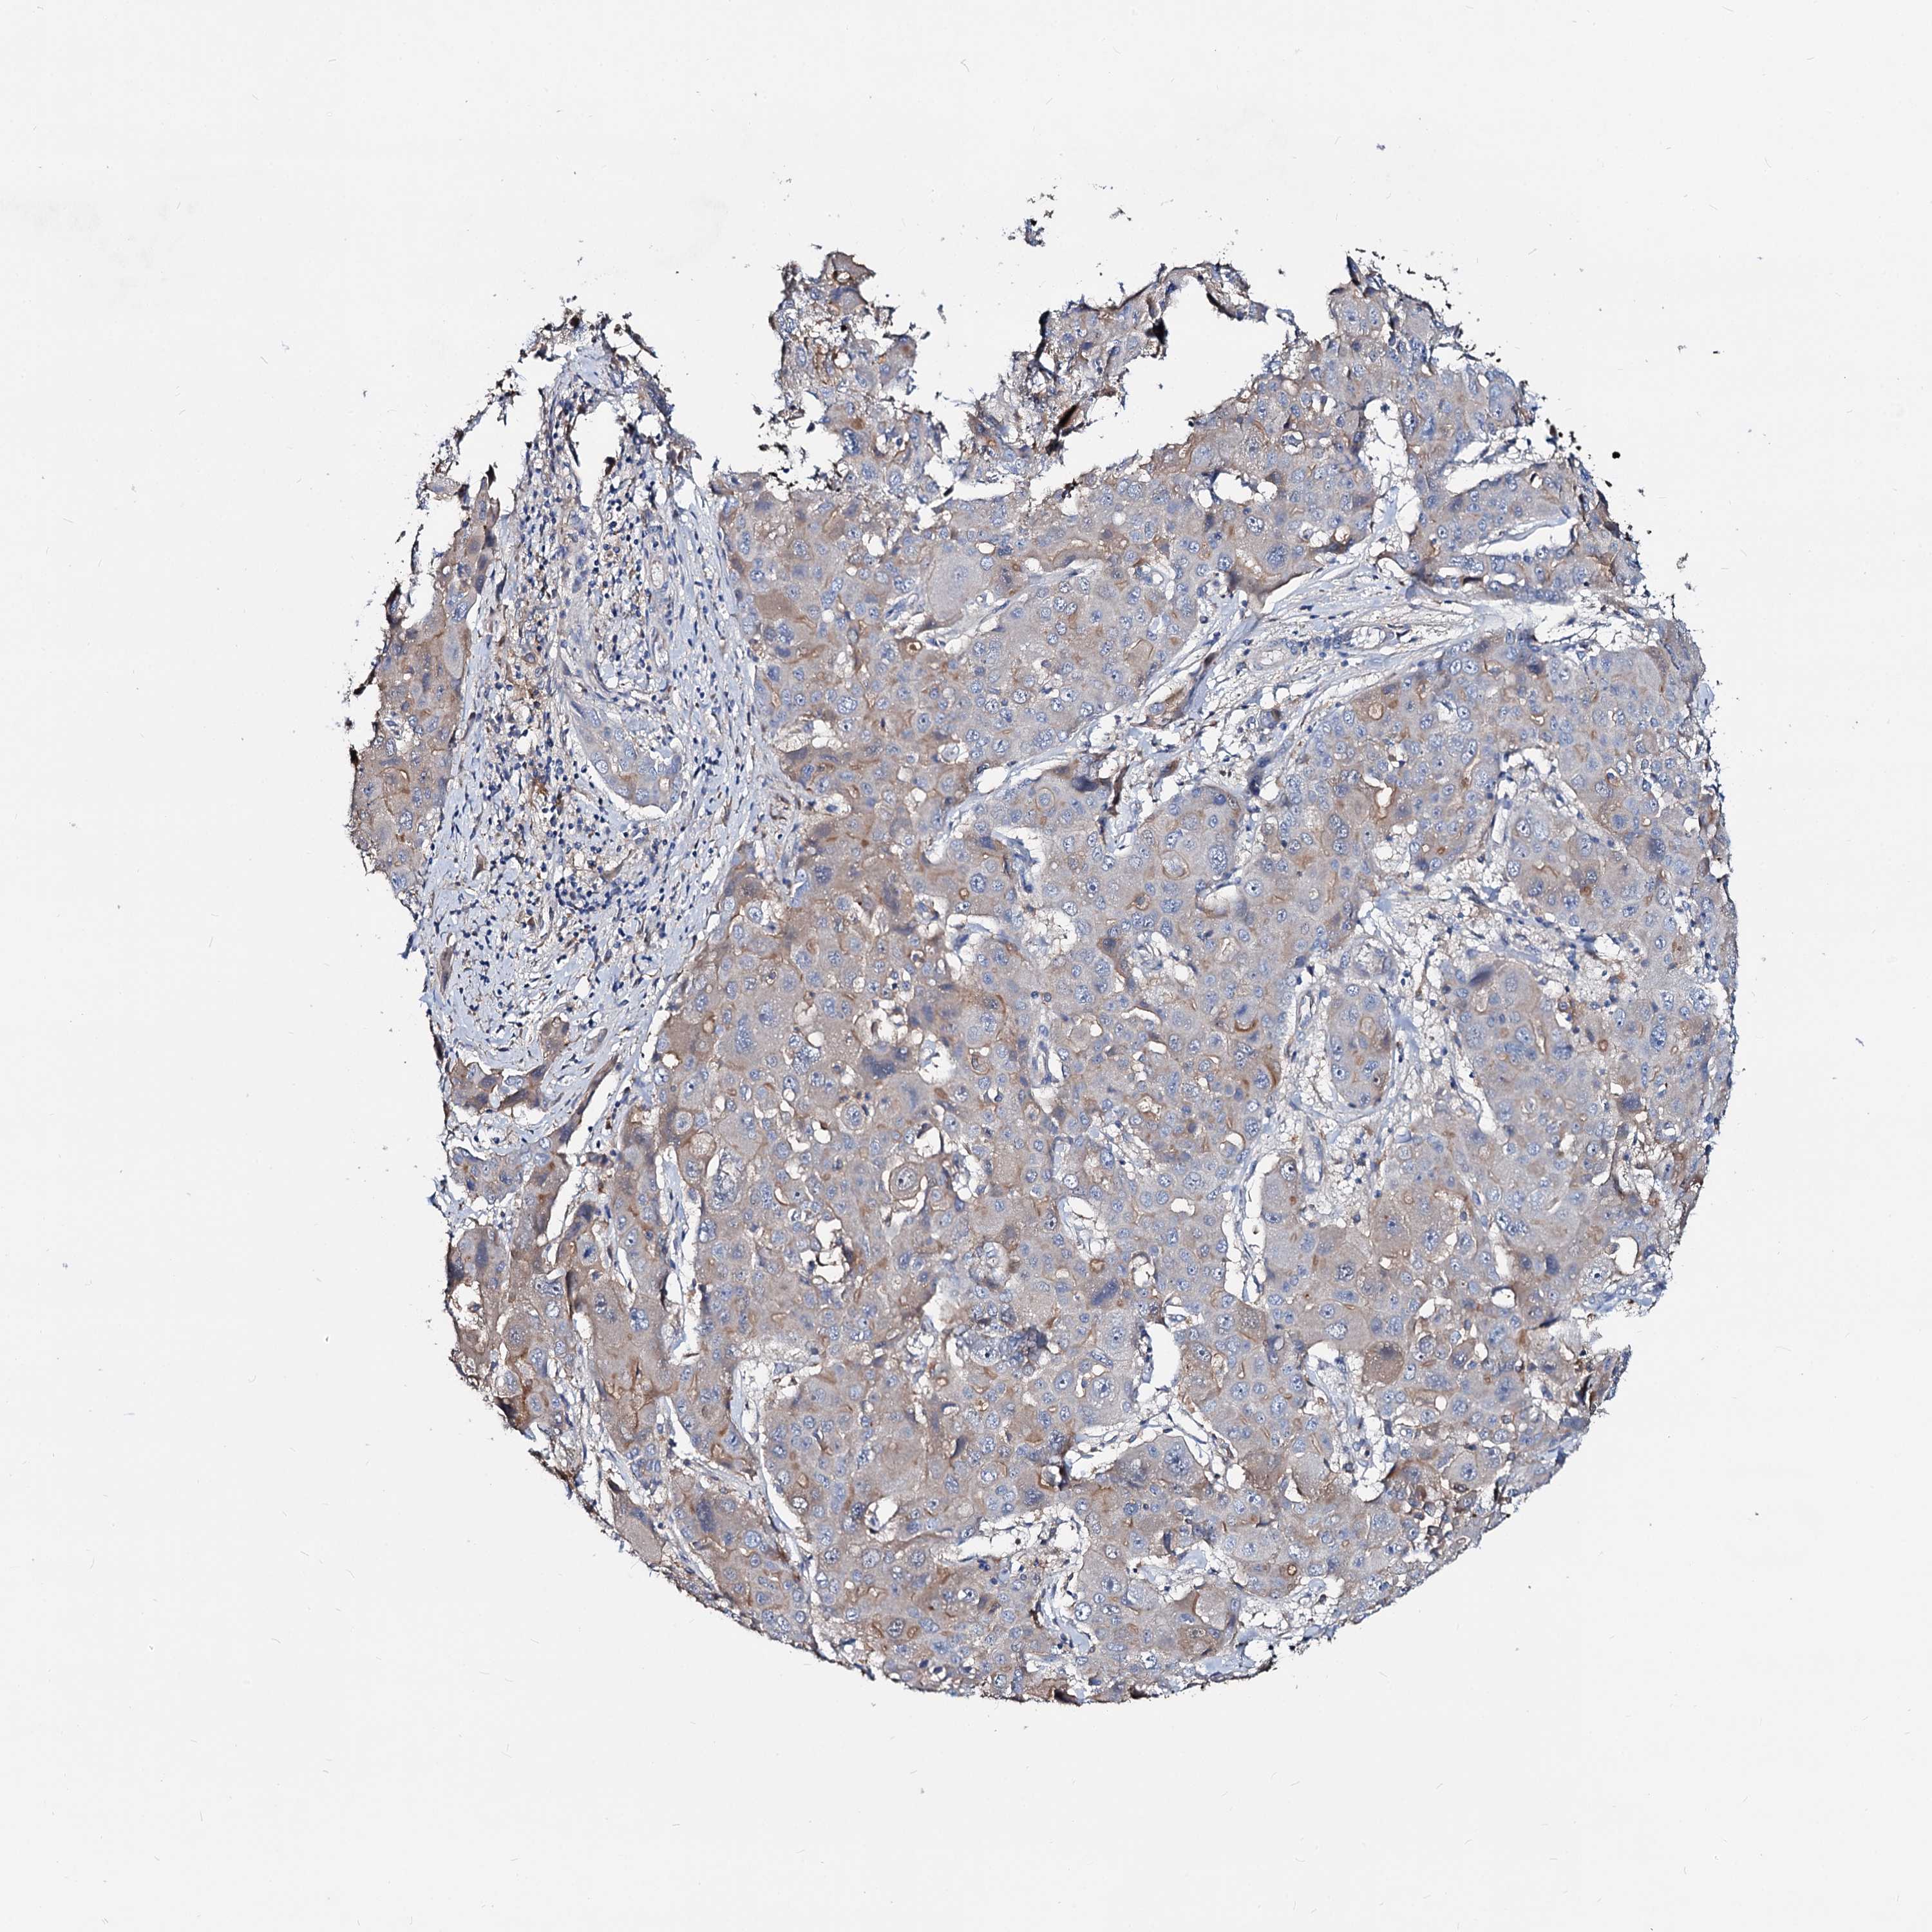

LIVER CANCER - Protein expressioni

A mouse-over function shows sample information and annotation data. Click on an image to view it in a full screen mode. Samples can be filtered based on level of antibody staining by selecting one or several of the following categories: high, medium, low and not detected. The assay and annotation is described here.

Note that samples used for immunohistochemistry by the Human Protein Atlas do not correspond to samples in the TCGA dataset.

Antibody stainingi

Antibody staining in the annotated cell types in the current human tissue is reported as not detected, low, medium, or high, based on conventional immunohistochemistry profiling in selected tissues. This score is based on the combination of the staining intensity and fraction of stained cells.

Each image is clickable and will lead to virtual microscopy that enables deeper exploration of all samples and also displays staining intensity scores, fraction scores and subcellular localization as well as patient and tissue information for each sample.

Antibody HPA039219

Antibody HPA048187

Staining

High

Medium

Low

Not detected

Intensity

Strong

Moderate

Weak

Negative

Quantity

>75%

75%-25%

<25%

None

Location

Nuclear

Cytoplasmic/membranous

Cytoplasmic/membranous,nuclear

Cholangiocarcinoma

Carcinoma, Hepatocellular, NOS